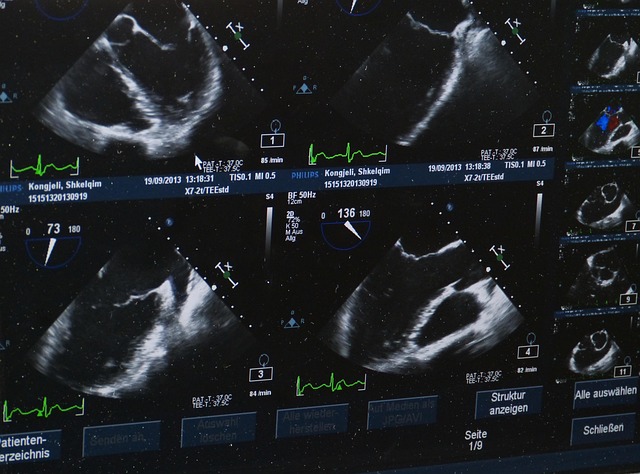

중장년 심장 건강 관리법에서 정기 검진은 선택이 아니라 필수입니다. 혈압, 혈당, 콜레스테롤 수치를 주기적으로 확인하는 것만으로도 심혈관 위험을 조기에 발견할 수 있습니다.

또한 가슴 불편감, 숨 가쁨, 극심한 피로 같은 작은 신호도 무시하지 않는 태도가 필요합니다. 중장년 심장 건강 관리법은 질병 치료보다 ‘조기 대응’에 더 큰 의미가 있습니다.